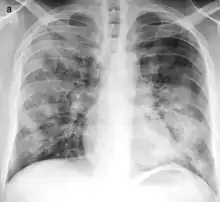

![]() | |

Typical distribution of lobar pneumonia (left in image) and bronchopneumonia (right in image) | |